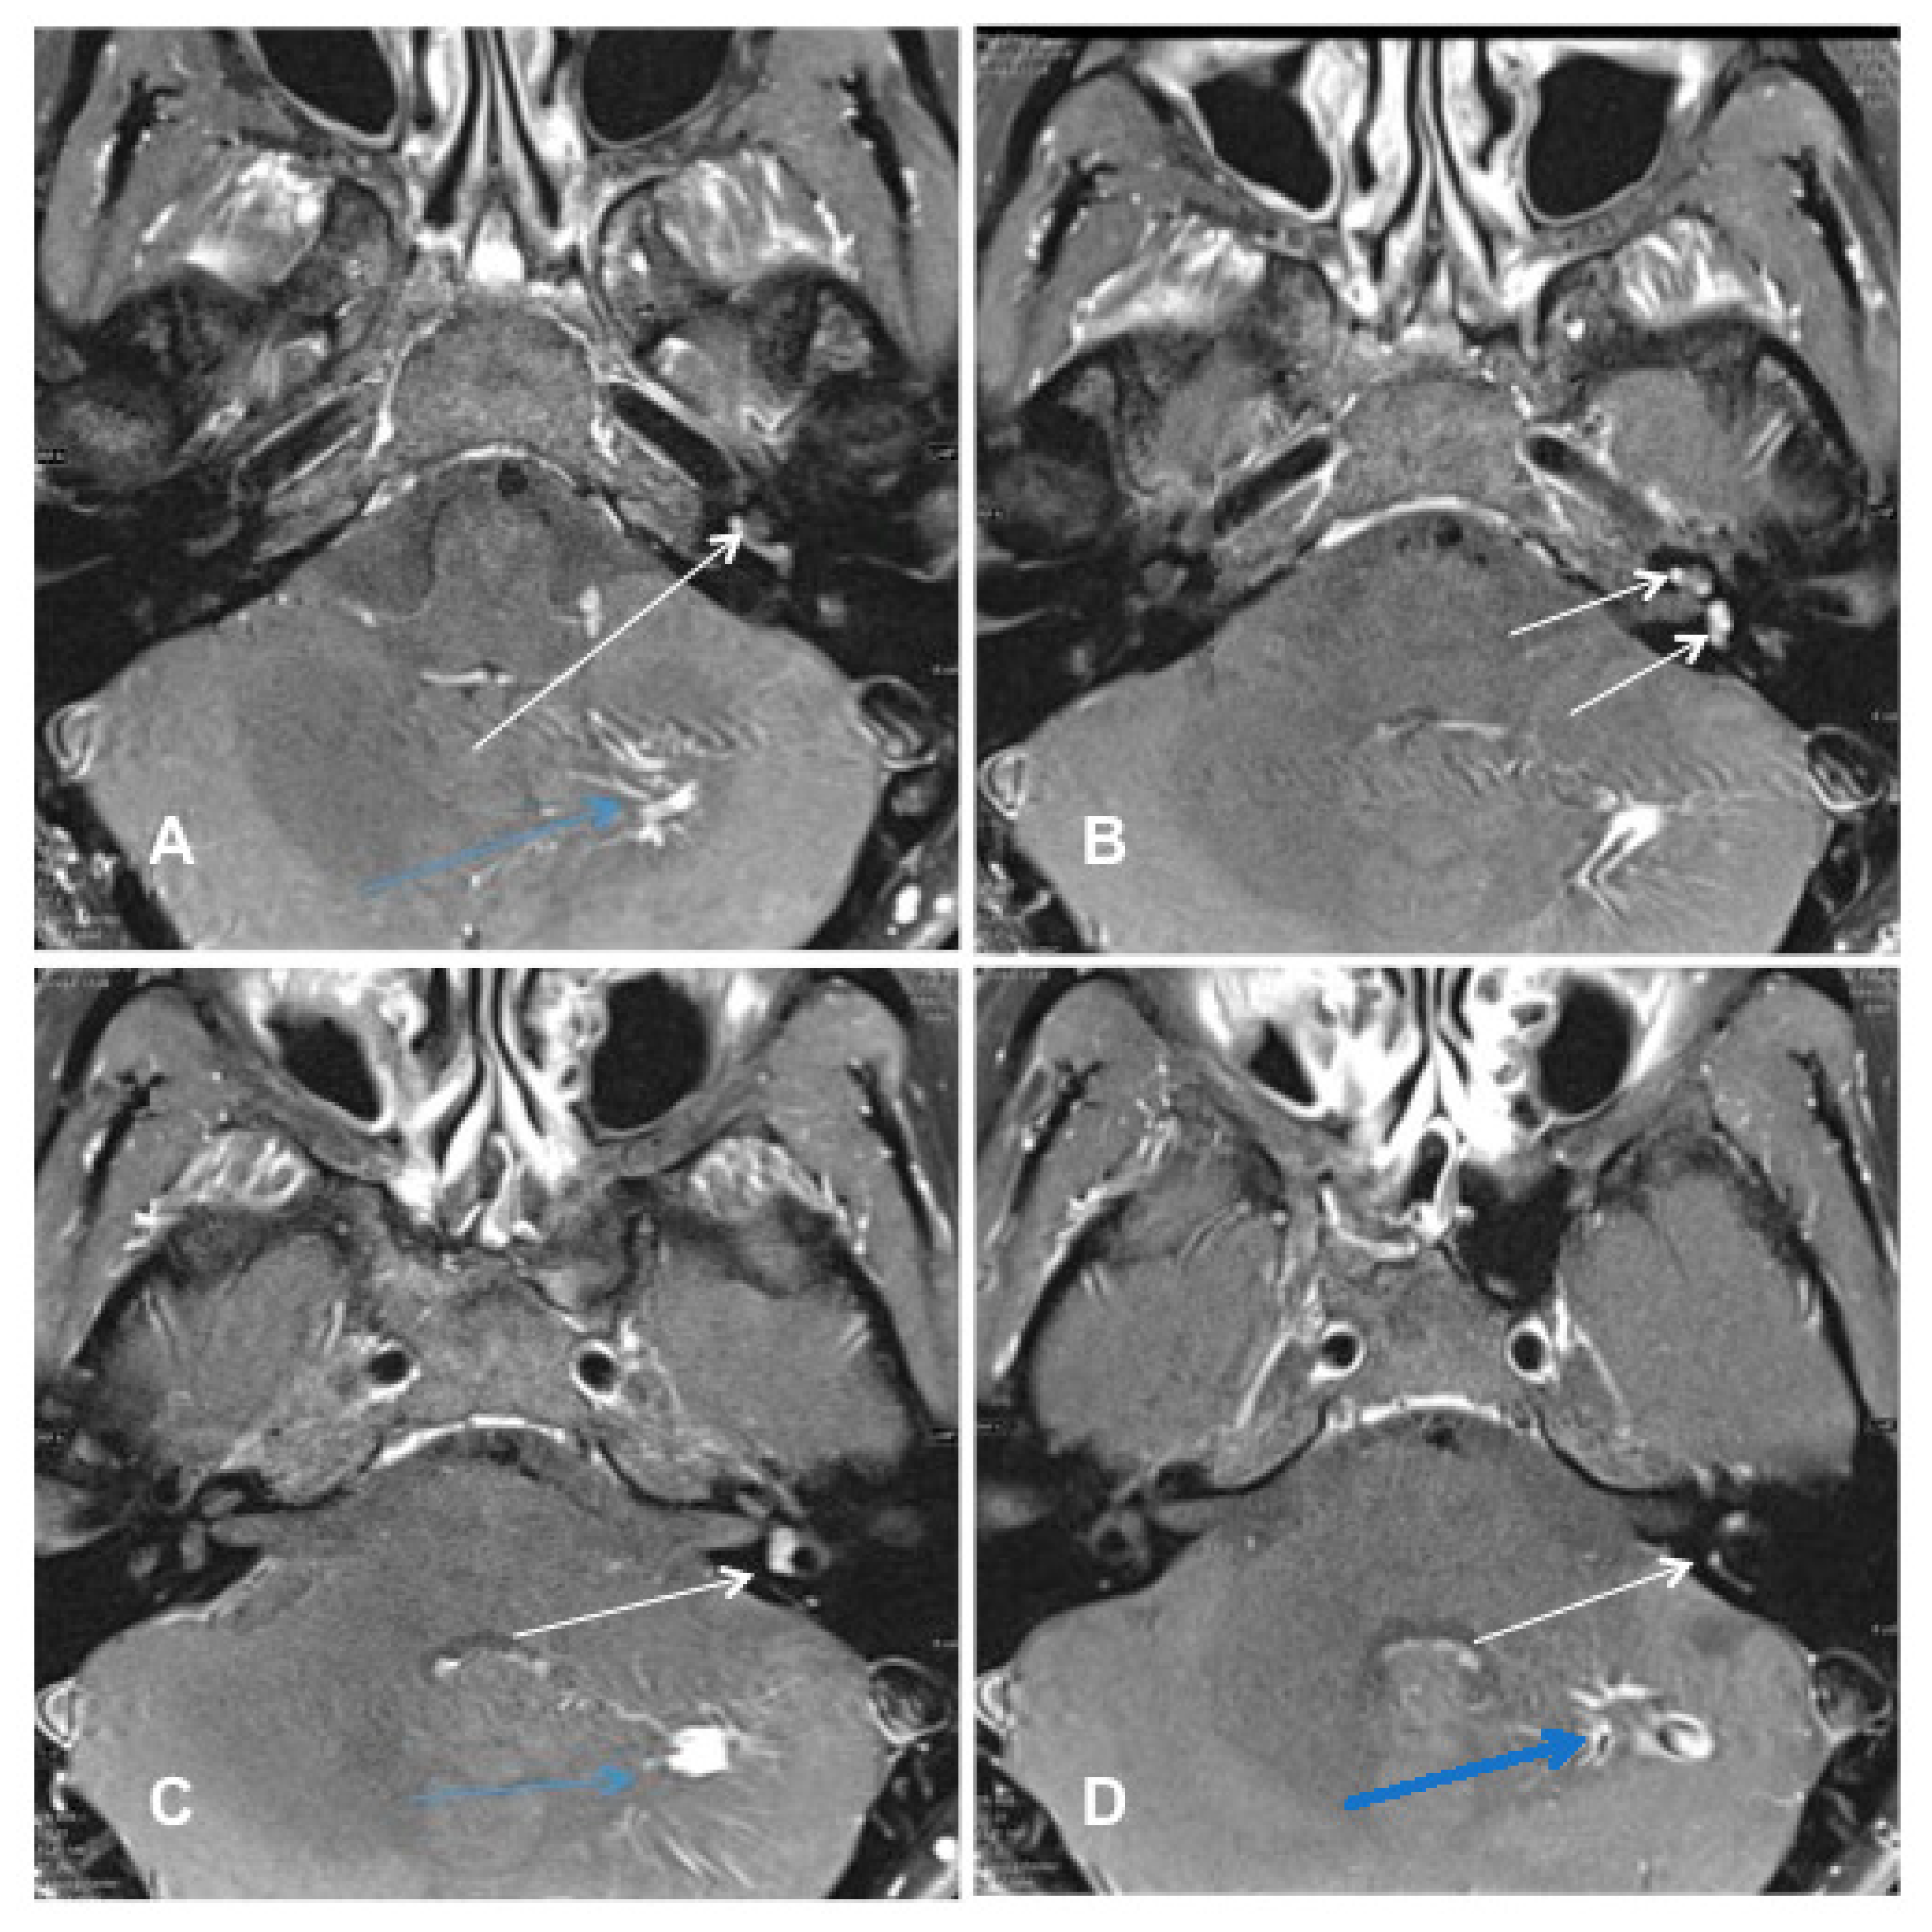

Patient #4 had an ILS of the middle cochlear turn of the left ear and intrameatal vestibular schwannoma of the right ear. Molecular genetic testing and clinical examination excluded neurofibromatosis type 2. cMRI visualized the ILS tumor mass on the left side and an intrameatal VS on the right side (Figure 4A–D). The patient opted for subtotal cochleoectomy with simultaneous cochlear implantation. Removing the incus and the crura of the stapes was necessary for optimal access to the cochlea during the surgery.

Figure 4. Case #4: MR images visualizing bilateral ILS (right side: intrameatal location, left side: intracochlear location). (A,B): T1 weighted VIBE 3D with fat saturation prepulse after the intravenous administration of gadolinium. (A) White arrows: intrameatal VS on the right side and ILS on the left side. (B) The white arrow points to the intracochlear schwannoma on the left side (middle turn); (C,D): T2 weighted SPACE sequences. (C) White arrows point to the intrameatal VS on the right and the ILS on the left. (D) The white arrow points at the ILS on the left side (middle turn).